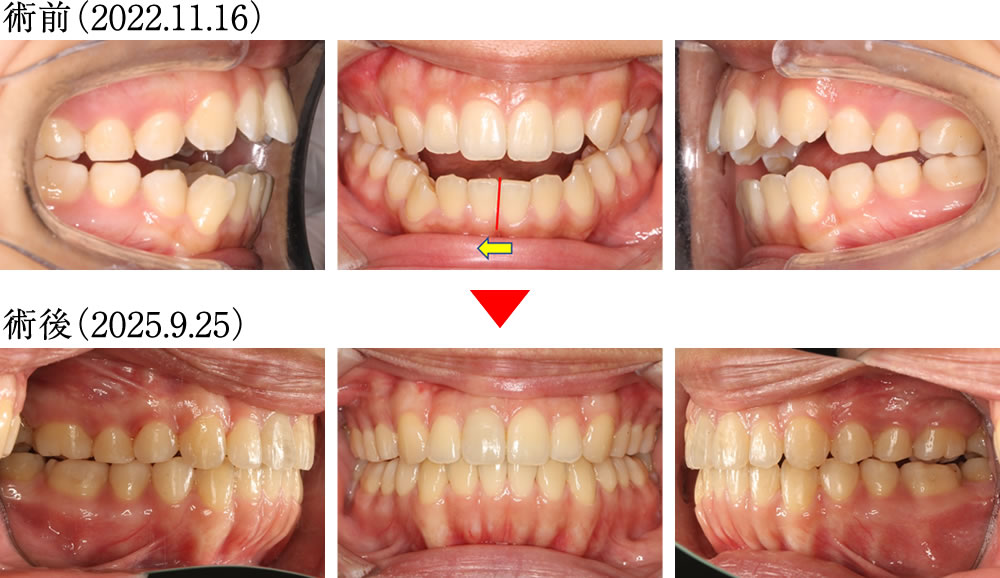

術前では、前歯が噛み合わず、上下顎の正中がズレた歯並びでした。術後は、上下の正中が揃い理想的な被蓋関係で噛み合ったキレイな歯並びになりました。

歯列が拡がったことにより、バッカルコリドー(笑った際に上の歯列と頬の内側との間にできる「黒い影」)が大きく改善されました。

術前は、前歯と犬歯がまったく機能していない歯並び・咬み合わせでしたが、術後は、前歯と犬歯が正しく機能する、理想的な咬み合わせとなりました。